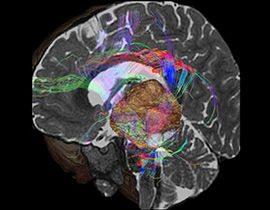

Mit der MRT können sowohl anatomische als auch physiologische Merkmale von Organen und Pathologien erkannt werden. Diese Vielseitigkeit macht die Bildgebungsmethode zu einem unverzichtbaren Diagnosewerkzeug. AW-Programme mit ihren vereinfachten Abläufen und intuitiver Benutzeroberfläche ermöglichen dem Anwender eine rasche und präzise Quantifizierung und qualitative Auswertung von MR-Untersuchungsergebnissen.

Erweiterte Visualisierung für MR